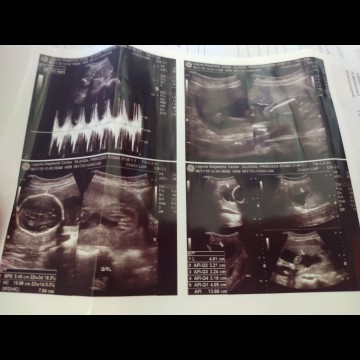

22weeks ultrasound

Hello po ask lang po how accurate kapag po 80% result gender ni baby. hehe sorry first time mom hndi lng nmn expect na girl sya mdmi ngsasabi n baka boy dw kasi hndi blooming etc. thank you mga mamsh 🙂